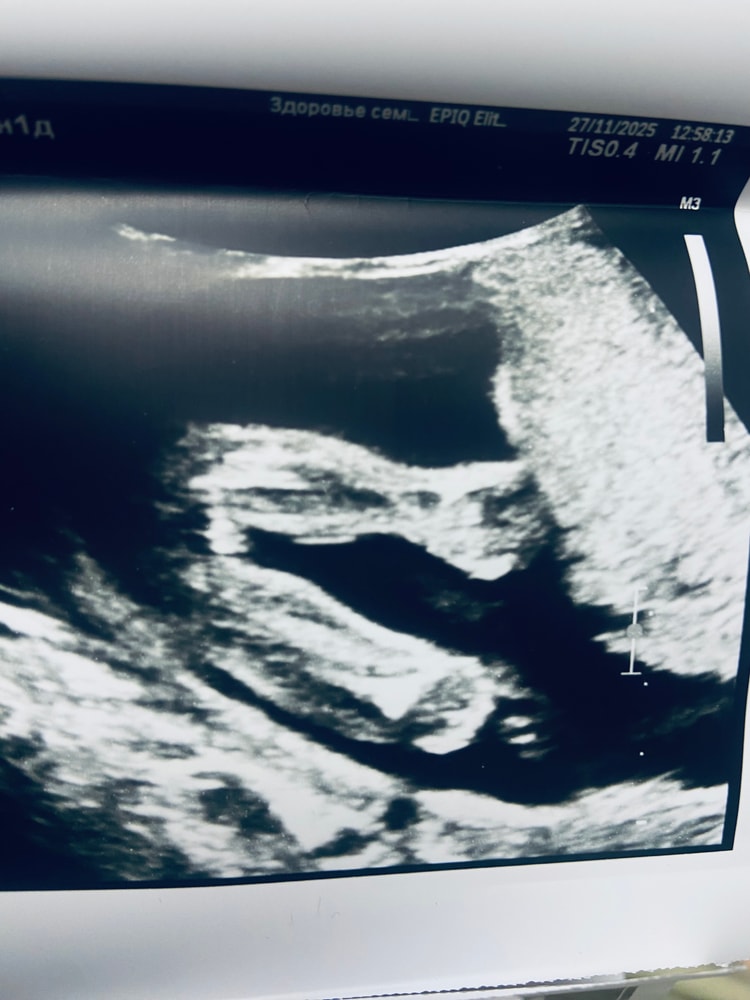

приложу фото , кого видите ?😀

Вижу девочку) похоже на кофейное зернышко